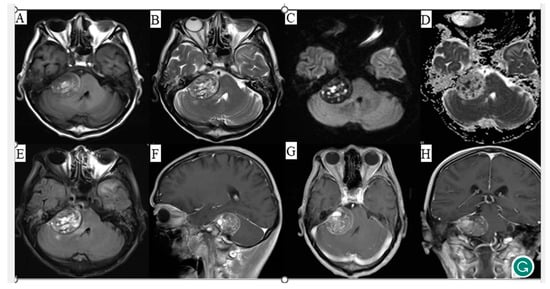

2. Case Presentation